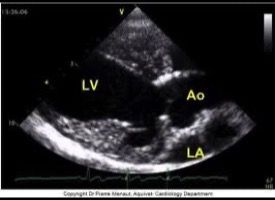

Sezioni Parasternali

Sezioni Apicali